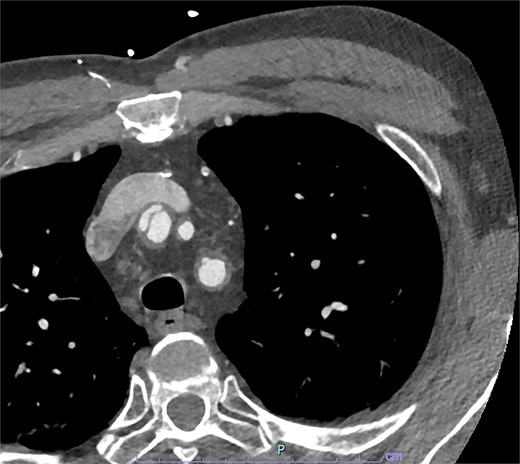

On arrive to the emergency department, the patient was found to be hypertensive with a blood pressure of 220/120 mmHg. Physical examination of the patient revealed no significant clinical findings. Serial troponins with corresponding ECG’s were undertaken which demonstrated no new evidence of myocardial ischaemia. Based upon the patient’s symptomatology, he underwent a CT aortogram which demonstrated a dissection arising from the proximal brachiocephalic artery. No dissection was noted in the ascending aorta, and there was no evidence of the brachiocephalic artery dissection extending into the subclavian or carotid arteries (Figs 1–3).

Axial slice from CT aortogram in greater detail of the dissection flap.